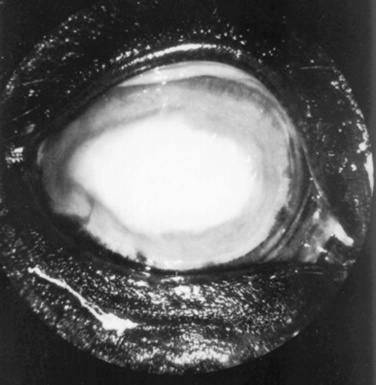

Corneal Lacerations

Corneal lacerations may be caused by sharp, protruding objects or projectiles. Corneal lacerations can occur with or without scleral laceration and, if they are nonperforating, may be treated as corneal ulcers. By contrast, perforating corneal lacerations must be repaired surgically. Preoperative preparation includes tetanus prophylaxis (horses and goats), systemic antibiotics, and sample collection for corneal culture and sensitivity. Ocular ultrasonography is very useful in determining the integrity of intraocular structures. However, care must be exercised during ocular examination, ultrasonography, and during surgery and anesthesia (especially induction and recovery) because extrusion of the intraocular contents may occur if excessive pressure is exerted on the globe or if the eyelids are forced open. In some cases, complete examination of the globe should be delayed until the animal is anesthetized.

General anesthesia, adequate magnification, proper instrumentation, appropriate suture material and needles, and adequate postoperative care are necessary for successful repair of a corneal laceration. Postoperative therapy must include topical antibiotics and mydriatics/cycloplegics, along with systemic antiinflammatory agents.34,37 The prognosis for recovery of vision and preservation of the globe generally is guarded. Complications that may occur after repair of corneal lacerations include phthisis bulbi, corneal fibrosis, synechia formation, blindness, retinal detachment, cataract formation, uveitis, endophthalmitis, bacterial or mycotic keratitis, and wound dehiscence with subsequent iris prolapse.

Page 1272

The prognosis after surgical repair of corneal or corneoscleral lacerations is best when the animal is presented immediately with a small wound in which the cornea or sclera is sealed and the anterior chamber has re-formed. Minimal hyphema, clear intraocular media, a clearly visible fundus, and laceration length of less than 15 mm are additional findings that indicate a favorable prognosis.33,36 In horses the success rate when only the cornea is involved is about 70% for recovery of vision and 90% for a cosmetically acceptable globe.33 With corneoscleral lacerations the prognosis is much worse. In our experience the success rate in such cases is 20% for recovery of vision and 70% for a cosmetically acceptable globe. Most phthisical globes are not considered cosmetically acceptable. Therefore, enucleation should be considered initially with severe corneoscleral lacerations because the prognosis is poor for return of vision and guarded for preservation of the globe. Several surgical procedures have been described in horses to provide a cosmetic appearance to the globe and orbit, including placement of an intraocular silicone prosthesis.38-40